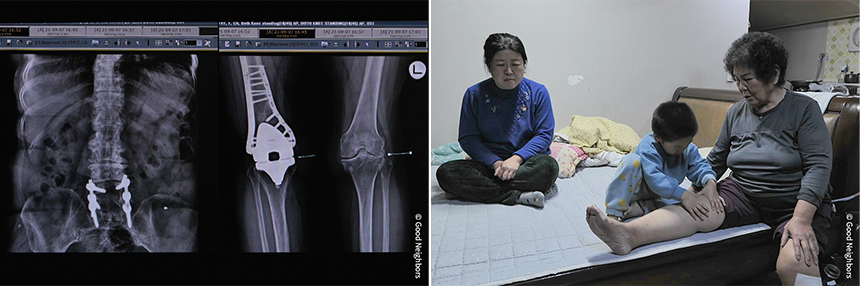

성준이의 엄마는 교통사고로 뇌 손상을 입어

시각장애와 뇌병변장애를 갖게 되었습니다.

단 한 번도 성준이의 모습을 눈에 담지 못한 채

손의 감각으로만 아이를 그리고 있습니다.

눈이 보이지 않는 엄마와

어린 손자를 지키고 있는 사람은

아픈 할머니뿐입니다.

마음과 달리 따라주지 않는 몸에

하루하루가 버겁기만 합니다.

점점 악화되는 통증을

진통제로 견디며 생활하고 있지만

할머니는 수술비 걱정에

선뜻 치료를 결정하지 못합니다.